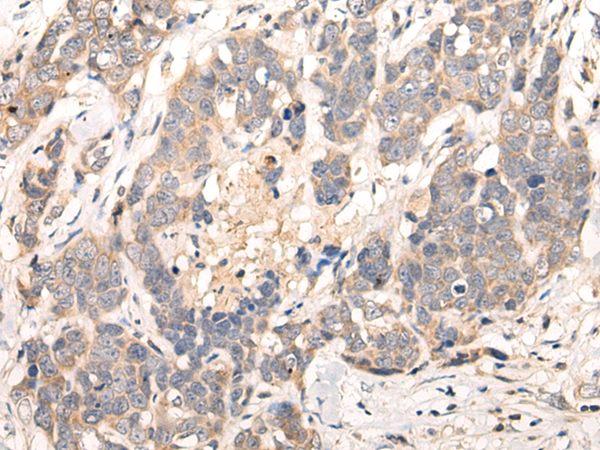

Applications:

ELISA, IHC

IHC positive control:

Human thyroid cancer and human ovarian cancer

IHC Recommend dilution:

10-50